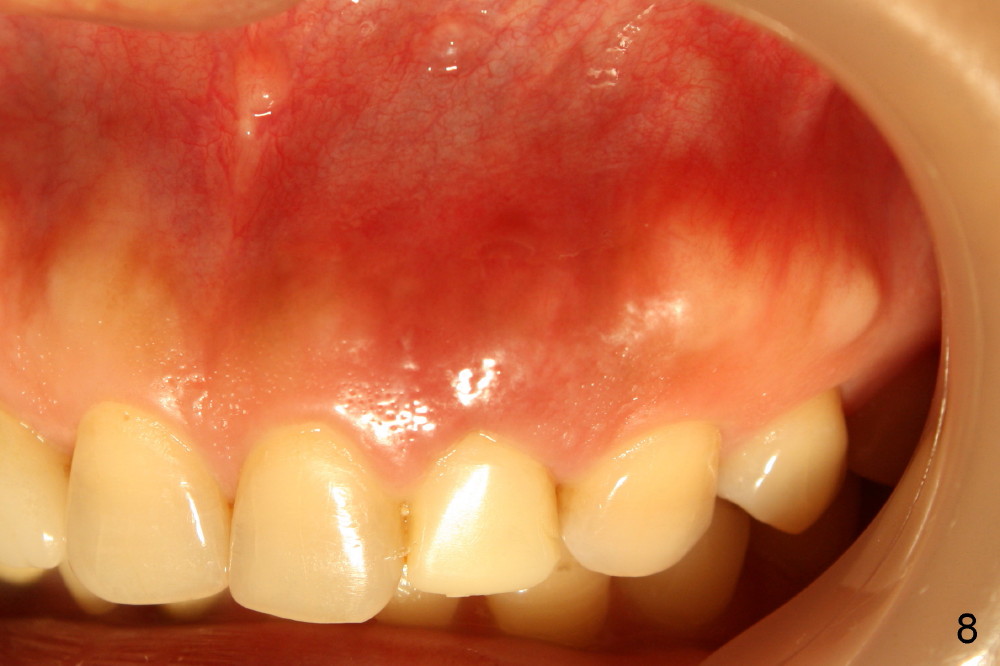

Within one week, the infection resolves (Fig.8,9).